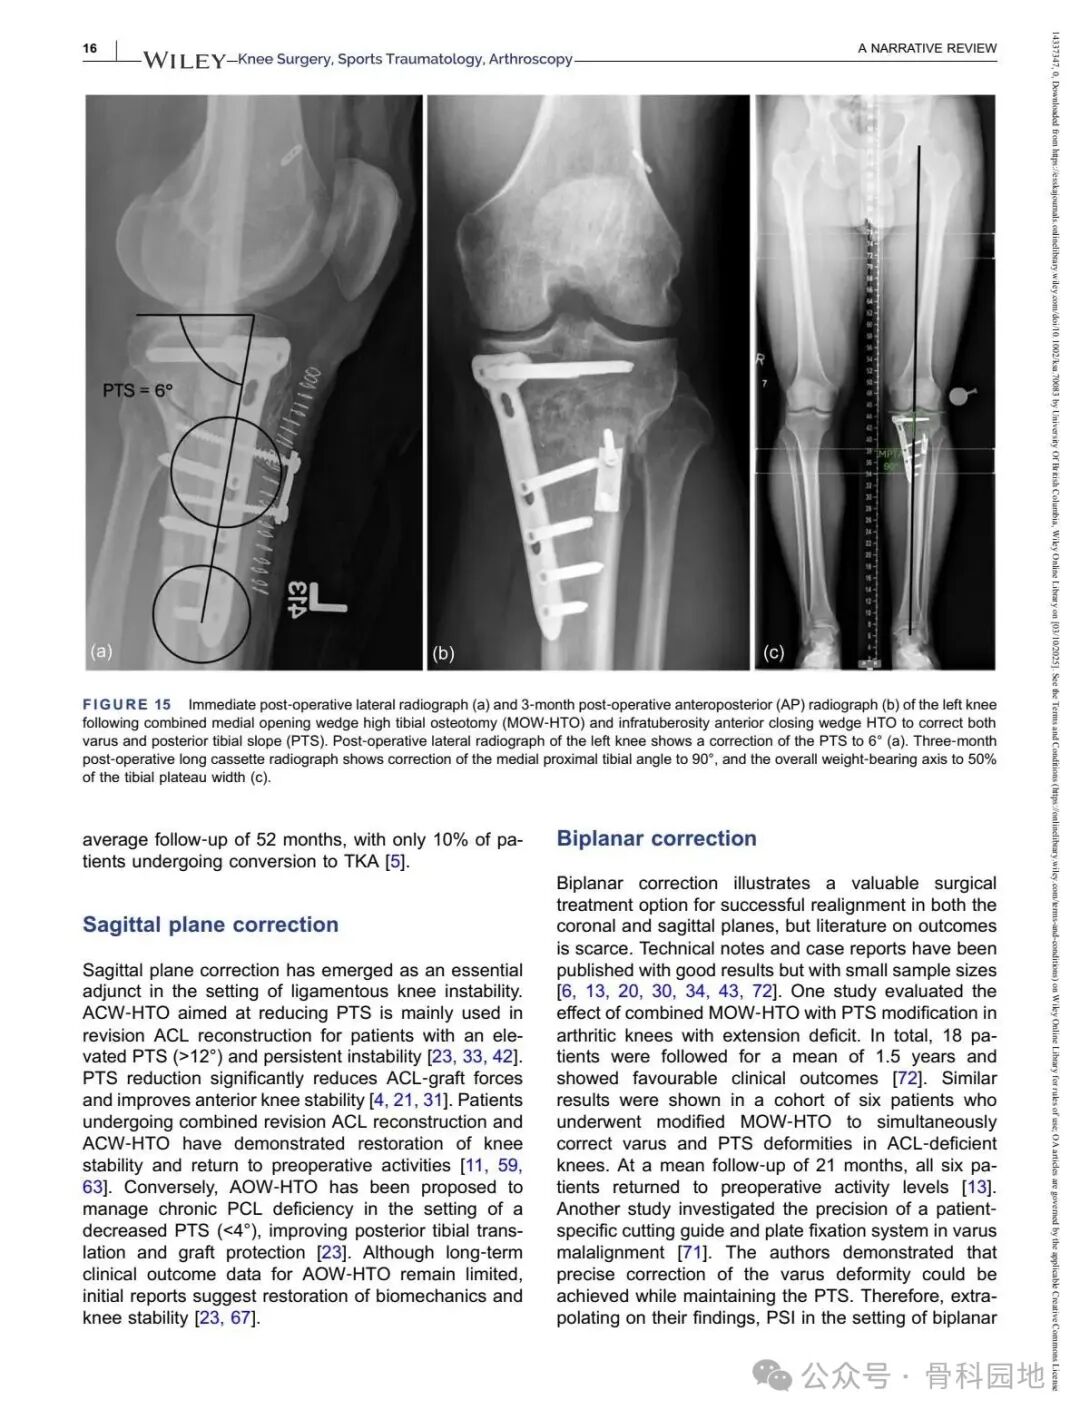

Although conventional high tibial osteotomy (HTO) primarily addresses coronal plane malalignment, the importance of sagittal plane alignment—specifically the posterior tibial slope (PTS)—cannot be overlooked in the setting of cruciate ligament insufficiency. Combined coronal and sagittal plane deformities are relatively rare and present unique surgical challenges. This narrative review summarizes the available literature and presents technical tips for managing complex biplanar deformities through a case‑based discussion of different techniques.